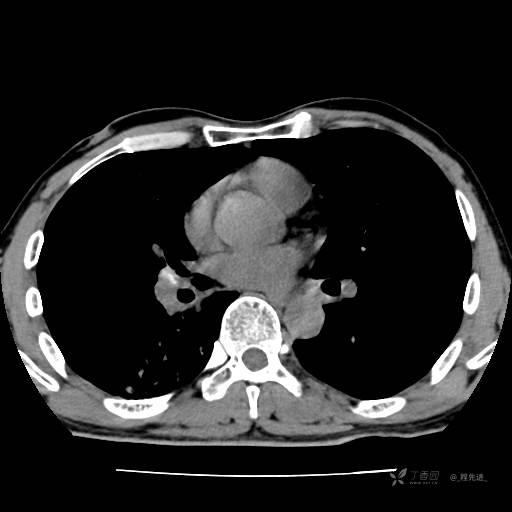

2月特别精彩病例|咳嗽、咳痰20余天,典型病例分享【结果已公布】

患者年龄:51岁

主诉:咳嗽、咳痰20余天

简要病史:20余天前开始出现咳嗽、咳痰症状,阵发性刺激性咳,白色粘痰,不易咳出,无发热,无咯血,无恶心、呕吐等不适,未诊治,咳嗽、咳痰症状持续存在。

体格检查:T:36.3 ℃ P:79 次/分 R:20 次/分 BP:128/64 mmHg,神志清楚,呼吸平稳,双肺呼吸音粗,右下肺闻及细湿性啰音。心率79次/分,节律整齐,各瓣膜听诊区未闻及病理性杂音。腹部未见异常,双下肢无水肿。

辅助检查:我院门诊胸部CT示:如下。心电图:窦性心律;正常心电图。